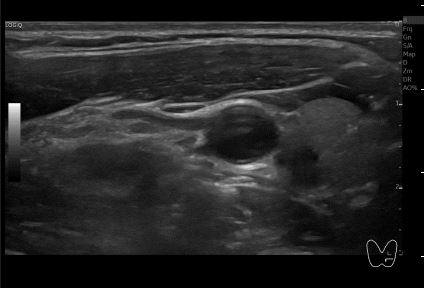

상기환자 외부검사상 이상 소견으로 내원하신 30대 여성분으로

의심스러운 갑상선 좌엽 세침검사 결과 갑상선암으로 진단되었습니다.